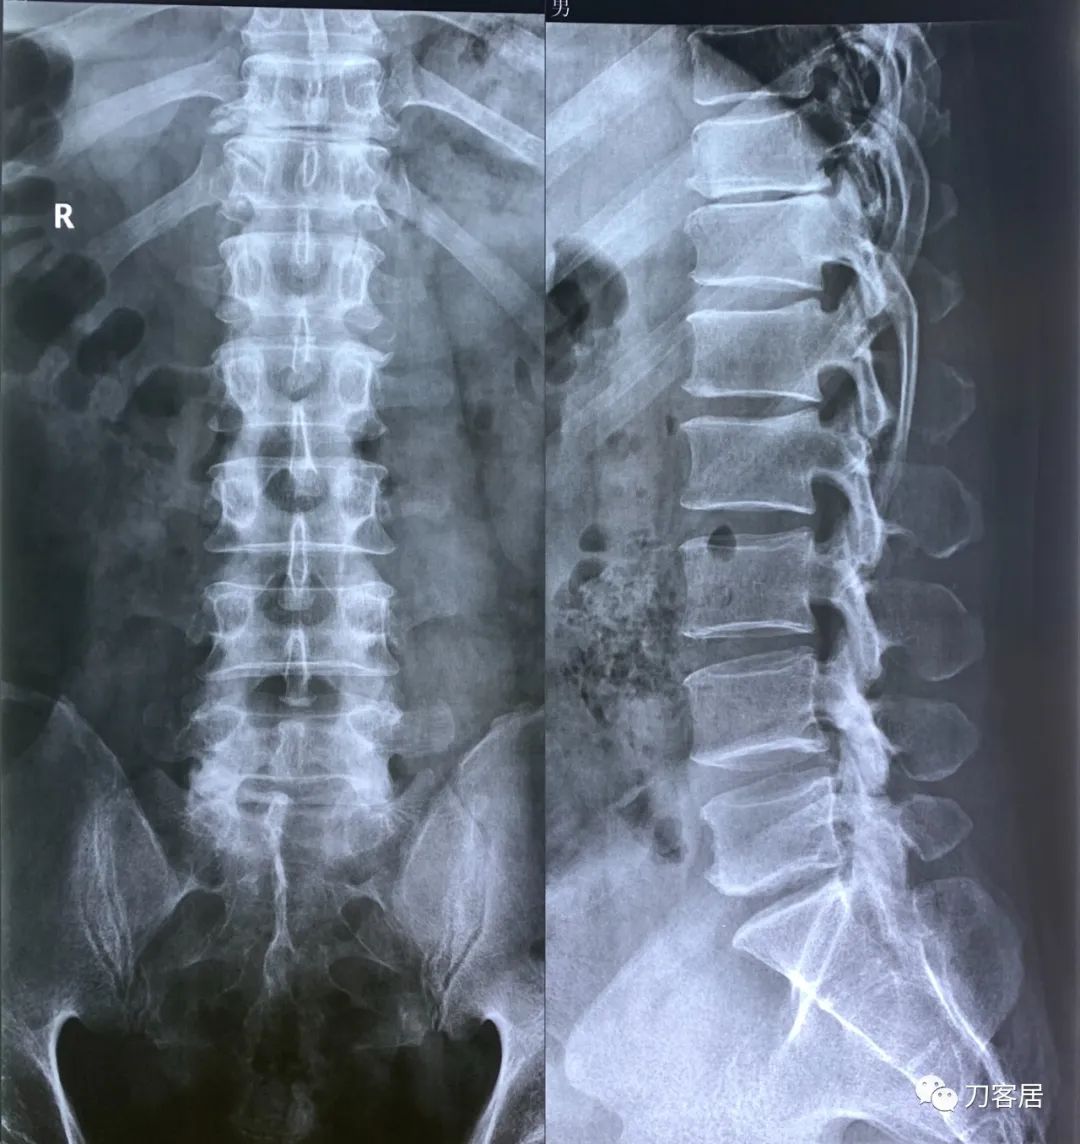

图17. 20220901西京医院胸椎正侧位X线片

图18. 20220901西京医院腰椎正侧位X线片,提示胸11-12椎间隙变窄。

图19. 20220901胸腰椎X线片报告